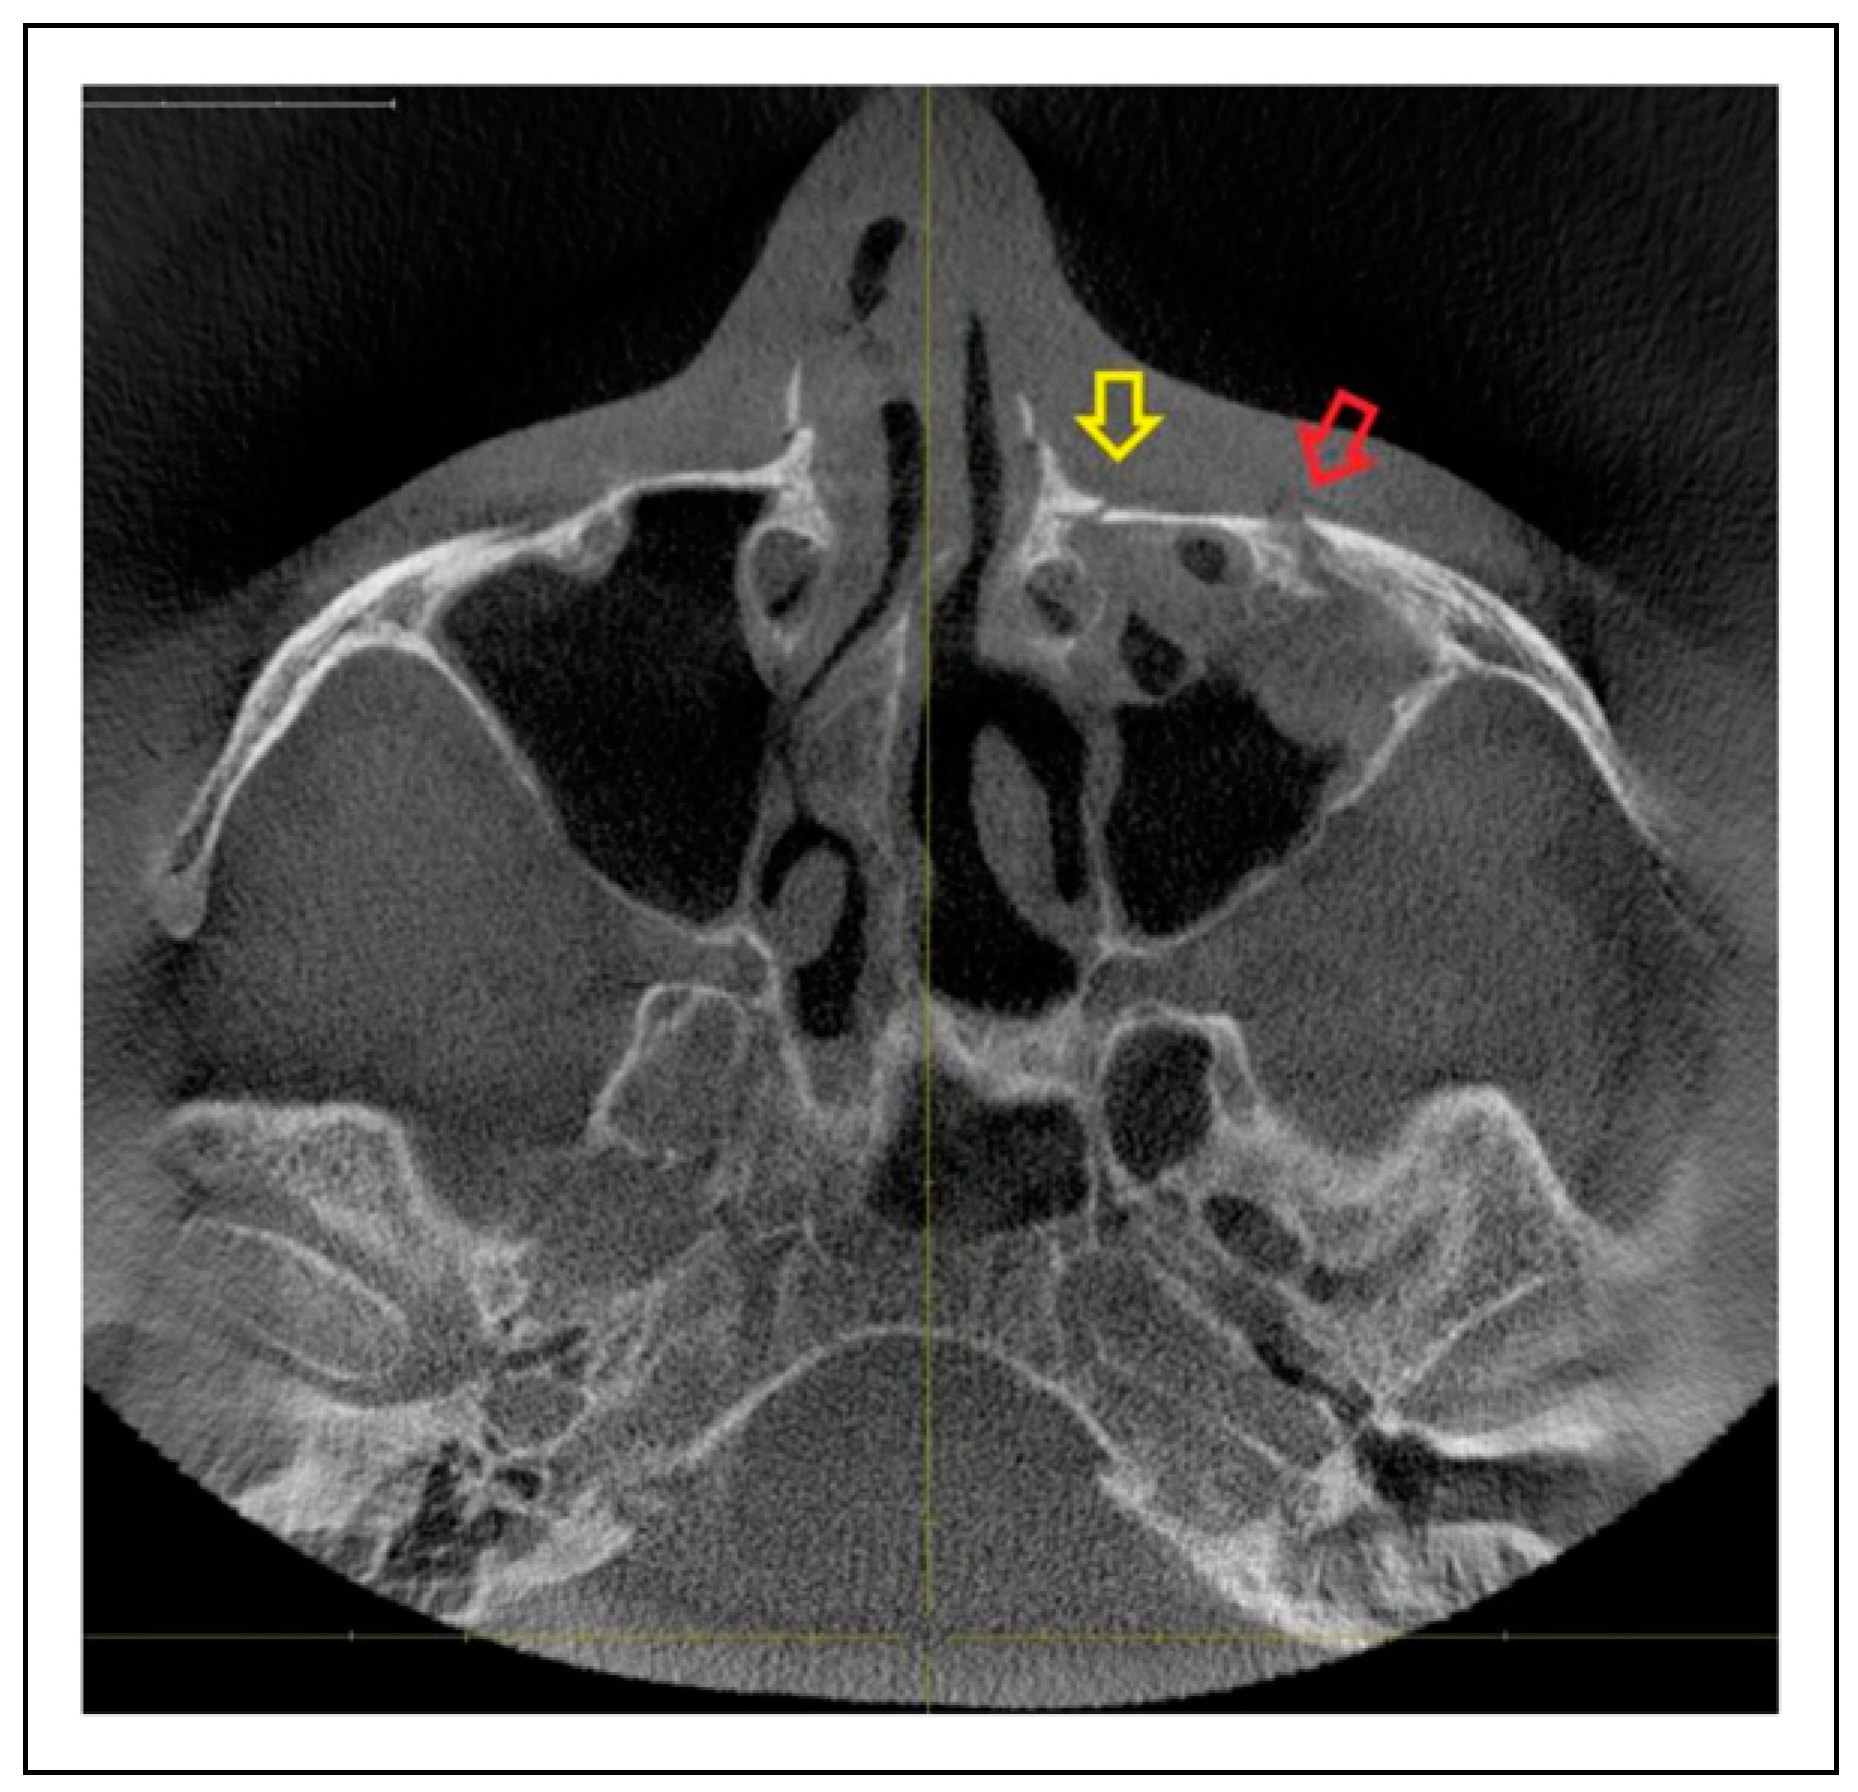

Patterns of ZMO Fractures Regarding the Anatomic Sutures of the Zygoma

- Unisutural fracture (isolated fracture of a single anatomic suture of the zygoma):

- Zygomaticomaxillary suture (ZM)

- Infraorbital rim (IOR)

- Zygomaticofrontal suture (ZF)

- Zygomaticosphenoidal suture (ZS)—the anterolateral orbital floor

- Zygomaticotemporal suture (ZT)

- Bisutural fracture with the following fracture line combinations: